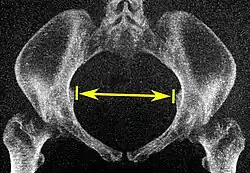

Pelvic inlet | Transverse diameter of the pelvic inlet | ![]() |

The iliopectineal lines, at widest transverse distance. | 13 to 14.5 cm.[4] |